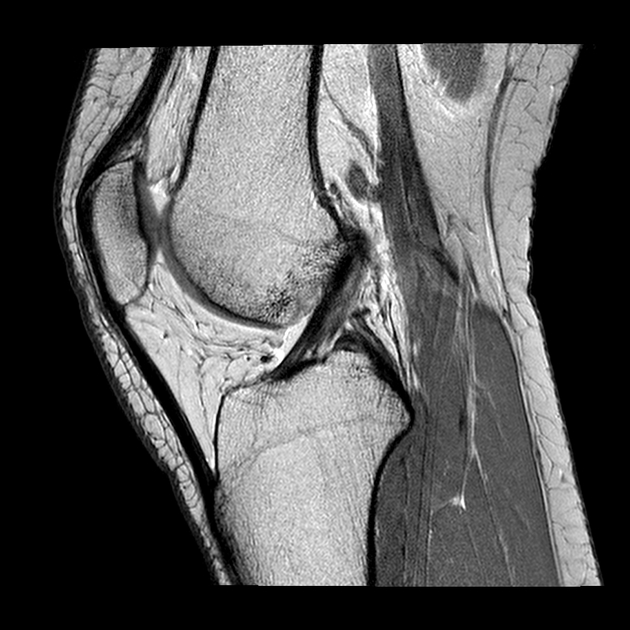

Crociato integro

Crociato Rotto

La diagnosi di lesione del legamento crociato anteriore è effettuata dall’ortopedico che, dopo aver effettuato degli specifici test ed aver studiato le immagini di Risonanza Magnetica, riesce a capire se il crociato è da operare e se sono presenti lesioni associate (danni della cartilagine, lesioni ai menischi, edemi ossei).

La Risonanza Magnetica nei casi di sospetta lesione del legamento crociato anteriore non andrebbe mai fatta prima di 10-15 gg dal trauma. Questo perché il sangue e il liquido accumulati nel ginocchio non permetterebbero una adeguata e corretta visione del legamento, rischiando di dire al paziente che il crociato è rotto quando in realtà non è così.